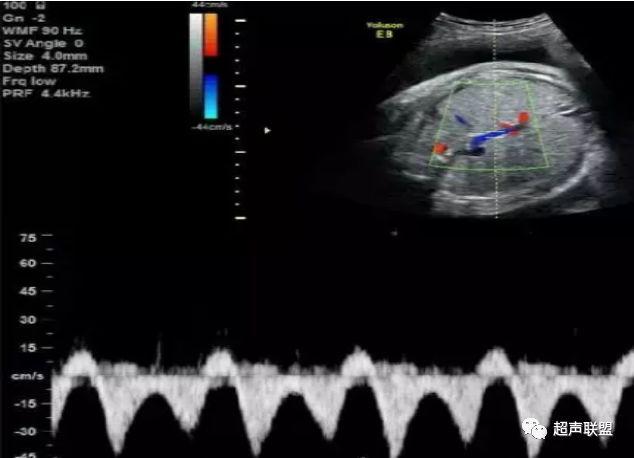

1 胎儿脐动脉测定

缺氧首先出现的变化是舒张末期血流降低,S/D值、RI值和PI值升高。当缺氧进入再分配晚期时,可逐渐出现舒张期血流减少、舒张期血流缺失。失代偿期出现脐动脉血液逆流,舒张期血流倒置。

1、比值标准:大脑中动脉阻力降低,妊娠期,大脑中动脉RI <脐动脉RI;

2、脐动脉标准:孕30周后,S/D>3;晚孕期,RI >0.75;孕18~20周后,脐动脉舒张期缺如或反向(后者见于严重的宫内缺氧者);

图1 正常脐动脉血流频谱

图2 脐动脉舒张期血流消失或反向